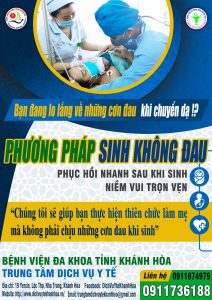

Đau trong khi sinh đẻ là gì? Khi tử cung co bóp để đẩy bé ra sẽ tạo những cơn đau làm cho mẹ lo